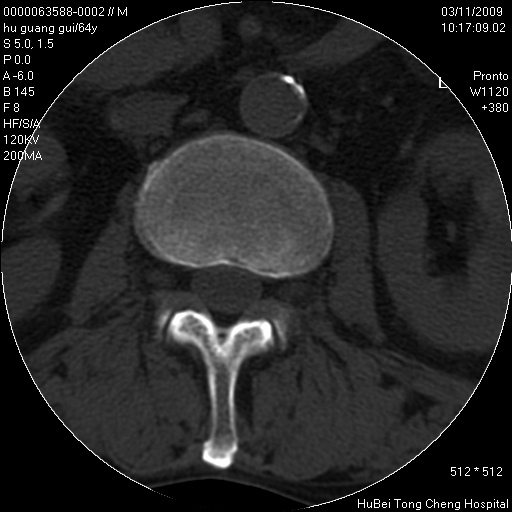

患者 男,64岁。腰痛十余天。(临床未提供其他病史)

临床诊断:腰痛原因待查(腰椎间盘突出症?)。

腰椎间盘ct轴位平扫(层厚5mm,层距4mm),图像如下:

腰椎退行性变,腰4—5椎间盘膨出。

右侧骶骨侧块骨侵蚀,骶髂关节骨性关节面破坏,并见软组织肿块,考虑骨转移瘤可能,进一步检查。

1.腰椎退行性变,腰4—5椎间盘膨出。

2.右侧骶骨侧块骨侵蚀,骶髂关节骨性关节面破坏,并见软组织肿块,考虑:脊索瘤,骨转移瘤可能,进一步检查。

1)腰椎退行性变,l4—5椎间盘膨出。2)骶骨右侧块骨转移瘤可能,3)水平骶椎。建议作一步检查。